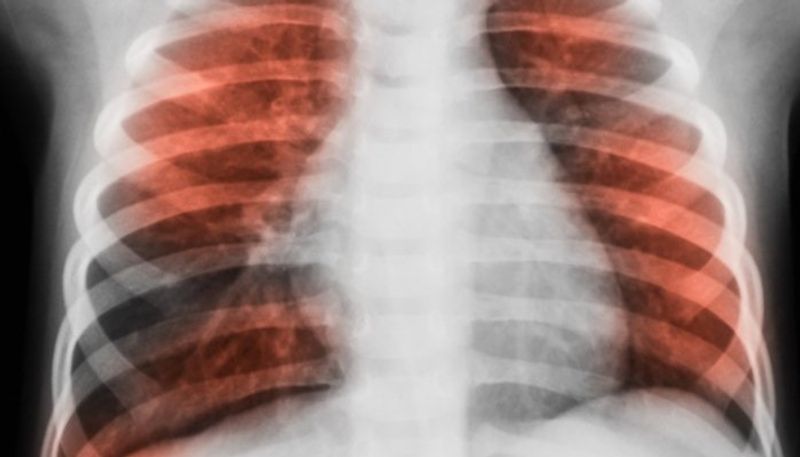

സിംഗപ്പൂരിലെ 'നന്യാംഗ് ടെക്നോളജിക്കല് യൂണിവേഴ്സിറ്റി'യില് നിന്നുള്ള ഒരു സംഘം ഗവേഷകര് ഈ വിഷയത്തില് ഒരു പഠനം നടത്തി. പഴകിയ ശ്വാസകോശരോഗമുള്ള 400 പേരില് നിന്നായി ശേഖരിച്ച സാമ്പിളുകളിലൂടെയാണ് ഗവേഷകര് പഠനം നടത്തിയത്. ഈ പഠനത്തിലൂടെ ശരീരത്തിനകത്തെത്തുന്ന രോഗാണുക്കള് ഒരു 'നെറ്റ്വര്ക്ക്' പോലെയാണ് പ്രവര്ത്തിക്കുന്നതെന്നും ഇവ തമ്മിലുള്ള ബന്ധത്തെ അടിസ്ഥാനപ്പെടുത്തിയാണ് അണുബാധയുടെ തീവ്രത മാറുന്നതെന്നും പഠനംസംഘം കണ്ടെത്തി.

ചില സന്ദര്ഭങ്ങളില് രോഗാണുക്കള് പരസ്പരം ഹസകരിച്ച് മുന്നോട്ടുപോകും. ഈ ഘട്ടത്തില് കാര്യമായ പ്രശ്നങ്ങള് കൂടാതെ തന്നെ രോഗിക്ക് ചികിത്സയെ നേരിടാം. എന്നാല് മറ്റ് ചില സന്ദര്ഭങ്ങളില് രോഗാണുക്കള് സഹകരിക്കുന്നതിന് പകരം തമ്മില് തമ്മില് മത്സരം നടത്തും. ഈ ഘട്ടത്തില് അണുബാധയുടെ ഗൗരവവും വര്ധിക്കുന്നു.